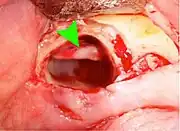

Impacted wisdom tooth with a backward tilt (distoangular impaction) and chronic infection to back of crown (green arrow)

Pericoronitis (green arrow) in lower right wisdom tooth

Impacted wisdom teeth without communication to the mouth, that have no pathology associated with the tooth, and have not caused tooth resorption on the blocking tooth, rarely have symptoms.[11] The chances of developing pathology on an impacted wisdom tooth that is not communicating with the mouth is approximately 12%.[11] However, when impacted wisdom teeth communicate with the mouth, food and bacteria penetrate to the space around the tooth and cause symptoms such as localized pain, swelling and bleeding of the tissue overlying the tooth. The tissue overlying the tooth is called the operculum, and the disorder is called pericoronitis which means inflammation around the crown of the tooth.[5]:141 Low grade chronic periodontitis commonly occurs on either the wisdom tooth or the second molar, causing less obvious symptoms such as bad breath and bleeding from the gums. The teeth can also remain asymptomatic (pain free), even with disease.[7]